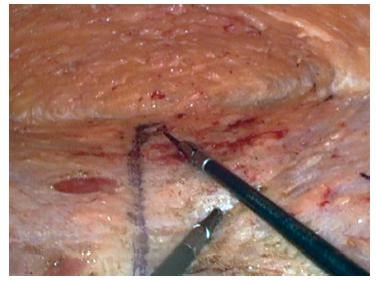

Операция SCOLA лишена этого недостатка. Её выполняют через три небольших прокола кожи в зоне бикини: 5-5-10 мм. В ходе операции хирург малоинвазивно при помощи лапароскопических инструментов освобождает из подкожной клетчатки белую линию живота и затем на всем протяжении сводит прямые мышцы специальной нитью. Во время операции возможно одномоментно решить вопрос с пупочной грыжей, с которой часто сочетается диастаз. При данном виде вмешательства использование сетчатого импланта определяется индивидуально и зависит от величины расхождения прямых мышц.

Операция SCOLA – подкожная пликация (ушивание) белой линии живота. Проводится через небольшие разрезы до 1 см в зоне бикини, которые в конце вмешательства ушиваются косметическим швом, поэтому видимых следов операции не остается.